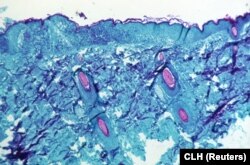

Главная неполитическая новость последних дней – вспышка так называемой оспы обезьян. Случаи заболевания зафиксированы уже более чем в полутора десятках стран, инфицированы больше ста человек. Всемирная организация здравоохранения созвала на прошлой неделе чрезвычайную сессию экспертов, чтобы обсудить ситуацию.

Человечество победило натуральную оспу более 40 лет назад, но с тех пор коллективный иммунитет ослаб, и нам все больше угрожают близкие вирусы – такие как вирус обезьяньей оспы. Это не новая болезнь, известно, что люди в Центральной и Западной Африке заражались этой инфекцией от обезьян и других животных как минимум с 1970-х. Но в последние годы случаев становилось все больше и они все чаще проникали за пределы Африканского континента.

Большинство людей болеют оспой обезьян достаточно легко, хотя летальность некоторых штаммов на порядок превышает летальность ковида. В то же время обезьянья оспа с трудом передается от человека к человеку, для этого нужно провести много времени в тесном контакте. Биолог и научный журналист Ирина Якутенко считает, что опасаться глобальной пандемии на этот раз не стоит. Но вирусы такого рода будут все больше угрожать человечеству и рано или поздно могут потребовать новой массовой вакцинации.